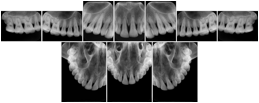

3. A dental provider wishes to capture a series of DICOM IO images for the patient’s dentition. The tooth morphology, teeth are divided into molars, premolars, canines and incisors, and a number of images for each jaw. The anatomic information was captured utilizing the triplet of schema. This standard code sequence is based on ISO 3950-2010, Dentistry - Designation system for teeth and areas of the oral cavity.

Every IO image should have anatomic information either through the primary or modifier sequence.

In most standard cases, images are oriented in structured layouts. These structured displays are useful to be shared between providers for reference purposes.

Table OO.1.1-1 shows structured display standard templates, where Viewset ID is based on the Japanese Society for Oral and Maxillofacial Radiology (JSOMR) classification provided by JIRA (Japan Medical Imaging and Radiological Systems Industries Association, www.jira-net.or.jp). Expected or typical teeth to be imaged location, region and designation codes are based on ISO 3950-2010, Dentistry - Designation system for teeth and areas of the oral cavity. For all the hanging protocols listed in OO.1.1-1, the value to use for Hanging Protocol Creator (0072,0008) is "JSOMR" and the value to use for Hanging Protocol Name (0072,0002) does not include "JSOMR" (e.g., "DL-S001A", not "JSOMR DL-S001A").